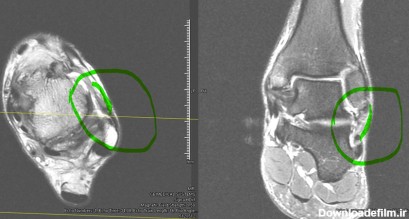

عکس ام ار ای پارگی رباط مچ پا

ام آر آی مچ پا یکی دیگر از اسکنهای شایع تصویربرداری پزشکی با ام آر آی است. در این اسکن به بررسی مچ پا ، پاشنه پا تاندون پا ، انگشتهای پا میپردازند.